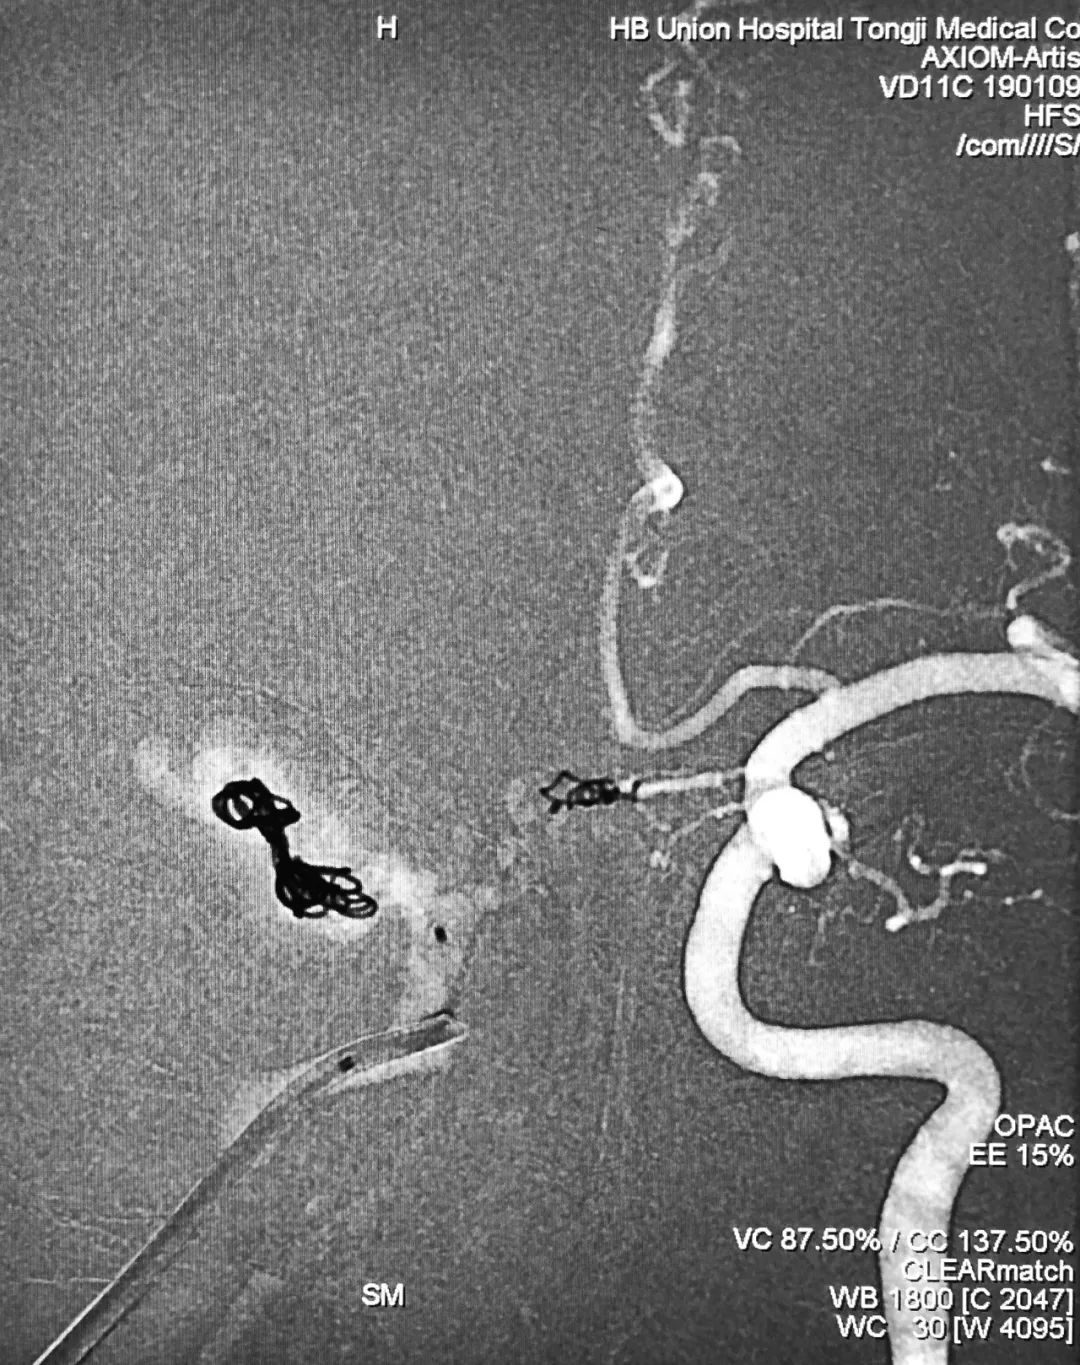

⑧ 术后左侧颈总动脉造影显示瘘口不显影:

将造影管移入右侧颈总动脉,正、侧位造影显示瘘口不显影:

正、侧位蒙片显示Onyx-18胶在右侧海绵窦内的铸型(约4.5 mm):